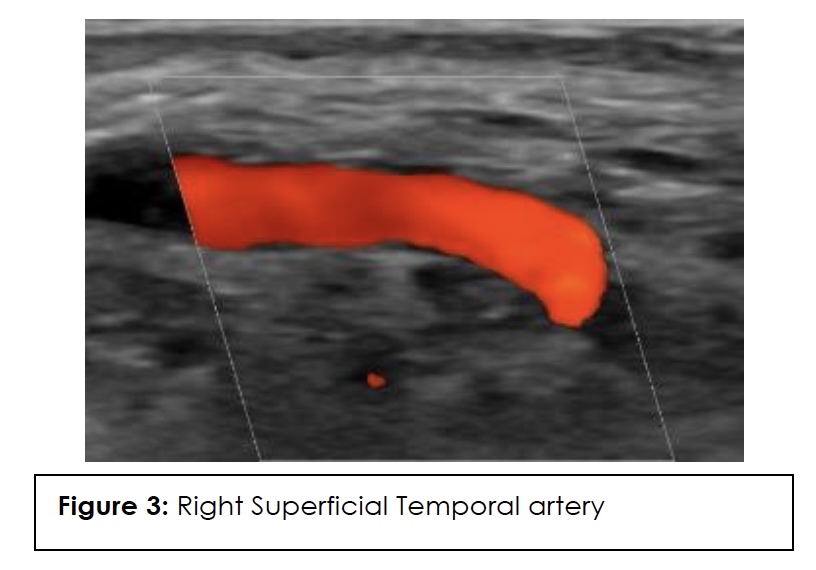

ESR, CRP, and color Doppler ultrasound (CDUS) of his temporal artery in July 2023 were negative, showing no GCA in the superficial temporal arteries. CDUS of bilateral temporal arteries demonstrated normal flow characteristics (Figures 1,2,3,4). Physical examination and temporal predominance of headache prompted obtaining the temporal artery biopsy in August 2023, which revealed healing GCA (Figure 5). The presence of myxoid change in the asymmetrically thickened intima and a residual infiltrate of mostly macrophages at the tunica intima-tunica media interface where the internal elastic lamina was absent allowed distinction of healing arteritis from age-related histopathological change, which may resemble healed giant cell arteritis. 3

In addition to laboratory results, color Doppler ultrasound (CDUS) of the temporal artery is now considered first-line for diagnosis because it has a higher sensitivity than temporal artery biopsy and is of lower cost and less invasive. The hallmark “halo sign,” visible on ultrasound, indicates inflammation of the vessel walls. Bilateral temporal “halo sign” is highly specific for GCA.36 In the 2016 TABUL study37 (a multi-center, prospective study for GCA), ultrasound had sensitivity of 54% and specificity of 81%, while temporal artery biopsy had sensitivity of 39% and specificity of 100%. Temporal artery biopsy remains the gold standard for diagnosis. The lower sensitivity of biopsy is likely due to skip lesions and prior corticosteroid treatment. Unexpectedly, our patient’s ultrasound was negative but biopsy was positive for GCA. Temporal artery abnormalities, including beading (irregular contour), prominence, tenderness, and an absent pulse, are reported to significantly increase the likelihood ratio for a positive temporal artery biopsy (TAB).38 Our patient had prominent temporal arteries on examination, giving him an increased likelihood of positive biopsy.

Ultrasound halo size abnormalities reduced after four or more days of high-dose glucocorticoid treatment. The percentage of positive biopsy results dropped significantly when patients began glucocorticoid treatment within 3 days.39 Our patient had the ultrasound performed approximately 20 days before starting the steroids, so the absence of the halo sign cannot be attributed to the steroids.